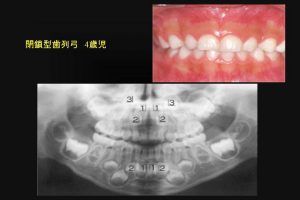

一方、閉鎖型歯列弓では、下顎の永久側切歯は中切歯より大きく写っている。

これは下顎の中切歯より、側切歯が舌側にあることを意味している。(図6)

なんらかの対策が必要だ。

図6

図6:乳歯の閉鎖型歯列弓は、下顎永久側切歯は、舌側へ萌出する可能性が高い。